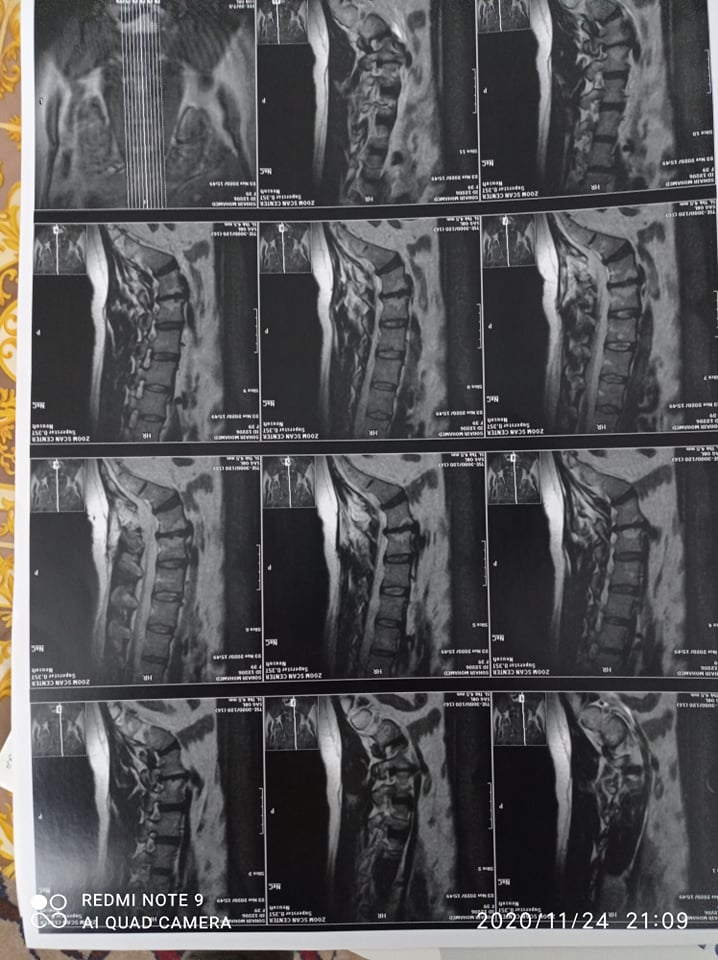

ناشدت المواطنة، سهير محمد علي، البالغة من العمر 39 عاما، في رسالة لخدمة القرّاء التي يقدّمها موقع "صدى البلد"، المسئولين فى وزاره الصحة،الموافقة على إجراء عملية تثبيت الفقرات القطنية على نفقة الدولة؛ حتى تتمكن من الحركة مرة أخرى.

وتقول فى رسالتها : انا محتاجه اعمل عملية تثبيت الفقرات القطنية، وتكلفة العملية كبيرة وانا حاليا بعانى من زيادة نسبة الألم وفشلت المسكنات في تسكين الألم بالاضافة الى عدم قدرتى على القيام بالأعمال اليومية بشكل طبيعي خاصة أنها عملية كبيرة ومن المحتمل حدوث بعض المضاعفات.

وناشدت القارئه، المسئولين بوزارة الصحة بأن ينظروا إليها نظرة رحمة وعطف، بالموافقة إجراء عملية تثبيت فقرات على نفقة الدولة ، نظرًا لعدم قدرتها على تحمل تكلفة العلاج .